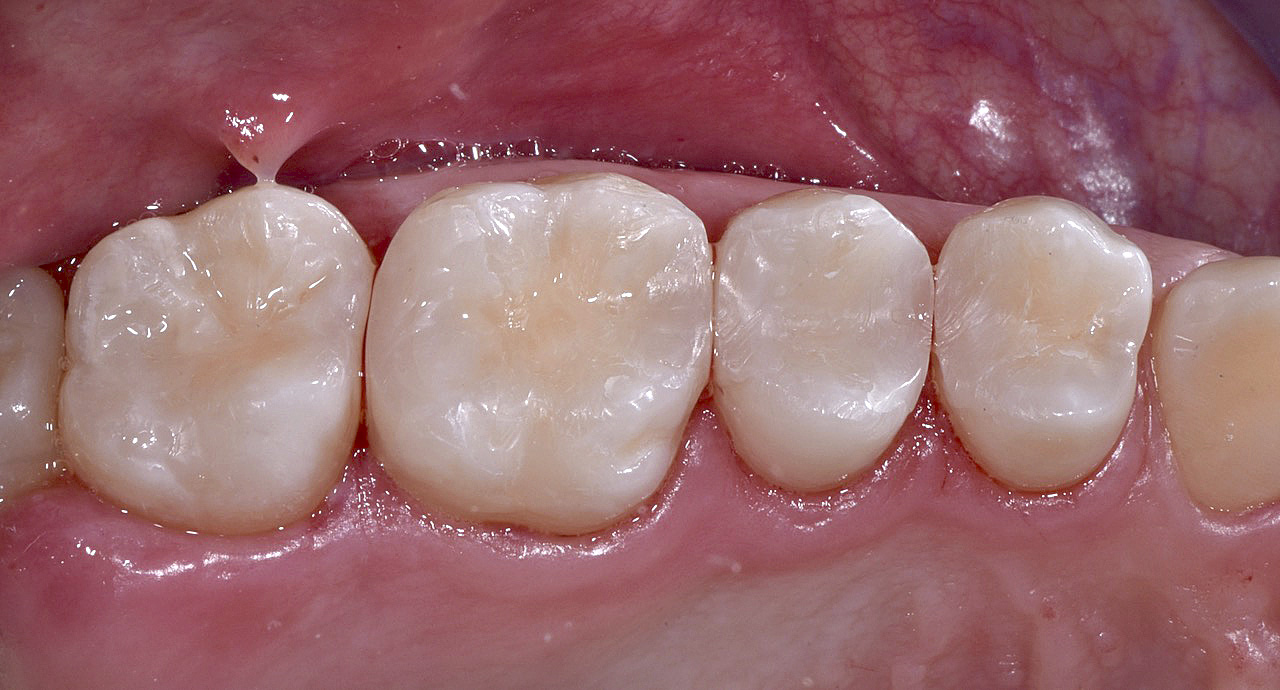

PREMESSA: in seguito all’estrazione dell’incisivo laterale superiore di destra, resasi necessaria per cause batteriche, si decide di affrontare il caso con il posizionamento di un impianto in sostituzione dell’elemento mancante dopo guarigione del sito infetto. Con tecniche rigenerative sia dei tessuti ossei mancanti a causa dell’infezione pregressa, sia dei tessuti gengivali che appaiono inizialmente troppo spostati in alto, si ripristina una corretta morfologia delle parabole (contorni) gengivali e delle papille interdentali (triangoli di gengiva tra due denti vicini).

Vengono utilizzati 2 tipi di provvisori: il primo, cementato ai denti vicini, viene utilizzato dal momento dell’estrazione del dente fino ad impianto osteointegrato (circa 6 mesi); il secondo, avvitato direttamente all’impianto, ha una funzione di prova estetica ma soprattutto di guida per la maturazione dei tessuti gengivali peri-implantari portandoli verso la maturazione completa prima di posizionare la corona finale in disilicato di litio.